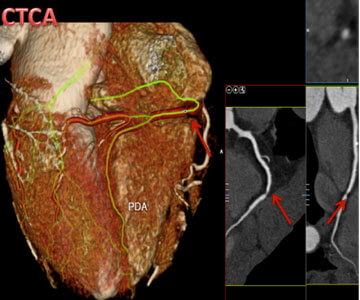

Example of CT Coronary Angiogram. Image on the left has both 3D/2D views and shows a severe narrowing in the right coronary artery (red arrow).

CT Coronary Angiogram is sometimes called Cardiac CT, and can be abbreviated to CTCA. CTCA enables direct visualization and assessment of the blood vessels of the heart for any narrowing and vessel wall content (calcium or cholesterol deposit). It also allows the evaluation of structures within the heart and outside the heart such as the aorta. If a significant narrowing or blockage is visualised on the CTCA, your treating Cardiologist will most likely refer you for an invasive coronary angiogram to further assess the narrowing.